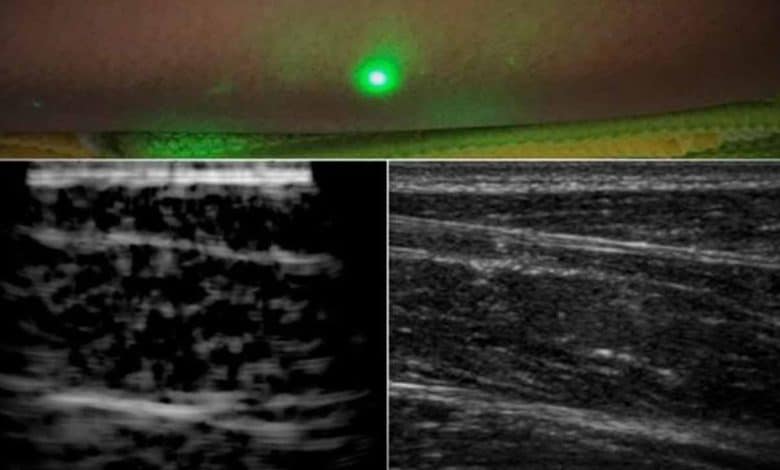

New York: Engineers at Massachusetts Institute of Technology have come up with an alternative to conventional ultrasound that does not require contact with the body to see inside a patient.

The new laser ultrasound technique leverages an eye- and skin-safe laser system to remotely image the inside of a person, which may one day allow doctors to assess the health of infants, burn victims, and accident survivors in hard-to-reach places from the comfort of their chambers.

In a paper published by Nature in the journal Light: Science and Applications, the team reported generating the first laser ultrasound images in humans.

The researchers scanned the forearms of several volunteers and observed common tissue features such as muscle, fat, and bone, down to about 6 centimetres below the skin.

These images, comparable to conventional ultrasound, were produced using remote lasers focused on a volunteer from half a metre away.

In this unconventional ultrasound method, when trained on a patient’s skin, one laser remotely generates sound waves that bounce through the body, said the study.

A second laser remotely detects the reflected waves, which researchers then translate into an image similar to conventional ultrasound, it added.